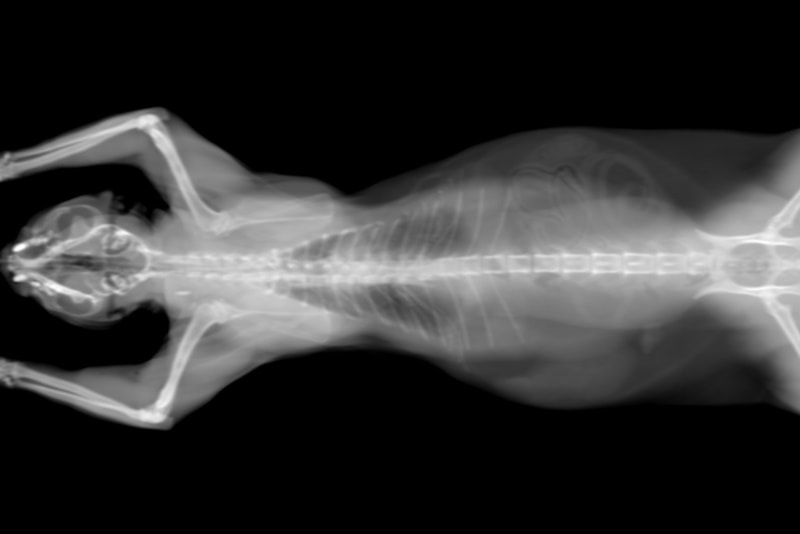

The only definite way to diagnose a brain tumor in cats is through certain imaging techniques (such as CT and MRI) and to determine the type of cancer, a biopsy. Since a brain tumor is a tumor of the soft tissue of the brain, you cannot see this on an X-ray of the skull. This usually means specialist involvement with a neurologist or oncologist.

black and white cat CT scan

Image By: Benny Marty, Shutterstock